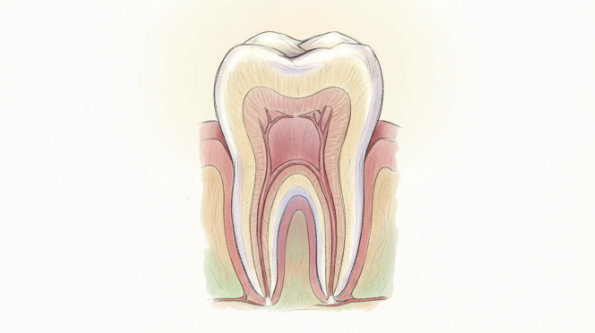

歯の内部には「歯髄(しずい)」と呼ばれる神経や血管の集まりがあります。虫歯が深く進行したり、外傷によって歯が傷ついたりすると、この歯髄に炎症や感染が起こります。そのまま放置すると、歯根の先端に膿が溜まり、強い痛みや腫れを引き起こします。

根管治療は、感染した歯髄を取り除き、根管内を丁寧に洗浄・消毒して、再感染を防ぐための詰め物をする治療です。

歯を抜かずに残すための、最後の砦とも言える処置です。

ただし、根管は非常に細く複雑な形状をしています。直径1mm以下の管が複数走っており、その形は歯によって大きく異なります。目視だけでは、根管の全体像を把握することは不可能です。だからこそ、レントゲンによる画像診断が必要になるのです。